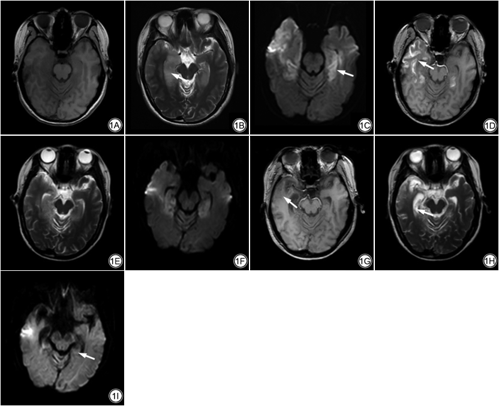

患者女,23岁,2021年6月16日无明显诱因下头晕不适,伴阵发性恶心呕吐,外院就诊示白细胞升高,予以抗炎治疗,症状稍好转。一日前突发言语混乱,记忆丧失,行为紊乱,伴发热,热峰38.8 ℃,遂至我院就诊,急查肝功能示钠128.9 mmol/L、氯91.6 mmol/L、尿素氮6.25 mmol/L、葡萄糖7.4 mmol/L、谷草转氨酶61 U/L、总胆红素25.4 μmol/L,脑电图示中度异常脑电图,额、中央区θ频段功率明显增强,6月18日以“精神异常原因待查”收住我院。6月21日头颅MRI示两侧颞叶内侧、右侧颞叶外侧及颞极、右侧岛叶片状等T1长T2信号,液体衰减反转恢复(fluid attenuated inversion recovery, FLAIR)呈高信号,扩散加权成像(diffusion-weighted imaging, DWI)示扩散受限,双侧海马肿胀提示自身免疫性脑炎或病毒性脑炎(图1A~1C)。同日查脑脊液N-甲基-D-天冬氨酸受体(N-methyl-D-aspartate receptor, NMDAR)抗体IgG 1∶1,血清NMDAR抗体IgG 1∶100,确诊为抗NMDAR脑炎。7月7日复查MRI示原脑实质内水肿病灶范围减小,并出现脑萎缩及病灶区沿脑回分布的线状短T1信号,其余序列信号较前相仿,考虑为新发脑皮质层状坏死(图1D~1F)。自6月21日确诊,患者采用丙种球蛋白0.4 g/kg•d联合甲强龙1 g冲击治疗(激素每5 d减半),7月11日查脑脊液NMDAR抗体IgG 1∶1,血清NMDAR抗体IgG 1∶10,7月12日出院前临时使用一次丙球抗体封闭血液中尚存抗体。8月18日复查MRI示上述水肿病灶进一步减小,脑萎缩加重,沿脑回分布的短T1信号消退,DWI扩散受限消退(图1G~1I)。

CLN的MRI表现具有特征性时间变化[10]:沿大脑皮质分布的脑回样T1WI高信号在病变发生后2周左右出现,此时易误诊为脑实质少许出血或蛛网膜下腔出血;T1WI高信号2周后逐渐显著,1~2个月时达到峰值,随后开始消退,最多可持续2年。本例起病2周左右复查MRI发现病灶区T1WI脑回样高信号,2个月后复查时消失,基本符合CLN的时间变化特征。